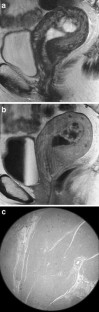

The endometrial cavity may demonstrate various imaging manifestations such as normal, reactive, inflammatory, and benign and malignant neoplasms. We evaluated usual and unusual magnetic resonance imaging (MRI) findings of the uterine endometrial cavity, and described the diagnostic clues to differential diagnoses. Surgically proven pathologies of the uterine endometrial cavity were evaluated retrospectively with pathologic correlation. The pathologies included benign endometrial neoplasms such as endometrial hyperplasia and polyp, malignant endometrial neoplasms such as endometrial carcinoma and carcinosarcoma, endometrial–myometrial neoplasm such as endometrial stromal sarcoma, pregnancy-related lesions in the endometrial cavity such as gestational trophoblastic diseases (hydatidiform mole, invasive mole and choriocarcinoma) and placental polyp, myometrial lesions simulating endometrial lesions such as submucosal leiomyoma and some adenomyosis, endometrial neoplasms simulating myometrial lesions such as adenomyomatous polyp and endometrial lesions arising in the hemicavity of a septate/bicornate uterus, and fluid collections in the uterine cavity (hydro/hemato/pyometra). It is important to recognize various imaging findings in these diseases, in order to make a correct preoperative diagnosis.

Fig. 1